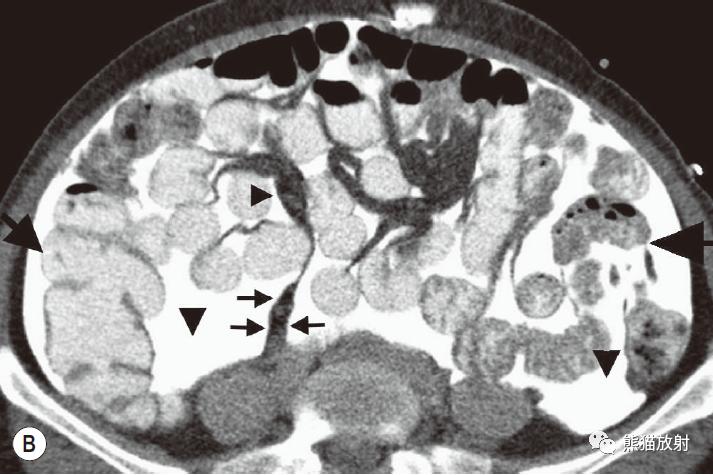

腹内疝:内脏通过腹膜或肠系膜孔突出形成。

包括:十二指肠旁(53%)、盲肠周围(13%)、Winslow孔(8%)、肠系膜和结肠系膜(8%)、乙状结肠间(6%)、吻合口后(5%)疝。

肠系膜疝。 扩张、充满液体的小肠襻丛位于前腹壁下的升结肠侧旁(箭),取代网膜脂肪。充盈的血管及邻近肠系膜模糊,折射了小肠绞窄性梗阻。